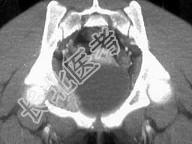

- 单项选择题青少年患者,臀疼, 最可能的诊断为 ( )

A、尤文肉瘤

B、骨肉瘤

C、动脉瘤样骨囊肿

D、骨纤维结构发育不良

E、以上都不是